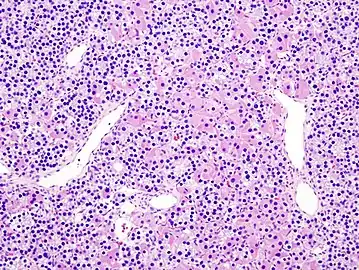

- Histopatholgical image of parathyroid adenoma in a patient with primary hyperparathyroidism. Hematoxylin and eosin stain.

- Histopatholgical image of parathyroid adenoma in a patient with primary hyperparathyroidism. Hematoxylin and eosin stain. Another view of the same lesion